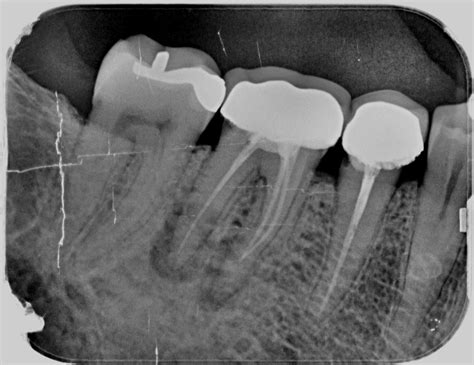

Radiografía de una endodoncia mal hecha

Una de las herramientas más seguras y fiables para detectar una endodoncia fracasada es la radiografía dental.

- Sobreobturación: cuando el material de obturación se extiende más allá de la raíz, puede irritar los tejidos periapicales.

- Lesiones periapicales: se identifican como áreas más oscuras o radiotransparentes alrededor del ápice del diente.

- Conductos no tratados: puede que existan conductos adicionales sin tratar, los cuales aparecen como áreas radiotransparentes, ya que no han sido limpiados ni rellenados.

- Fracturas radiculares: aunque a veces son difíciles de detectar, pueden verse como líneas finas y oscuras a lo largo de la raíz.

En estas imágenes se observa una lesión radiotransparente alrededor del ápice del diente, con una endodoncia bien hecha en principio, pero fracasada finalmente, y su posterior curación radiográfica tras una cirugía periapical.